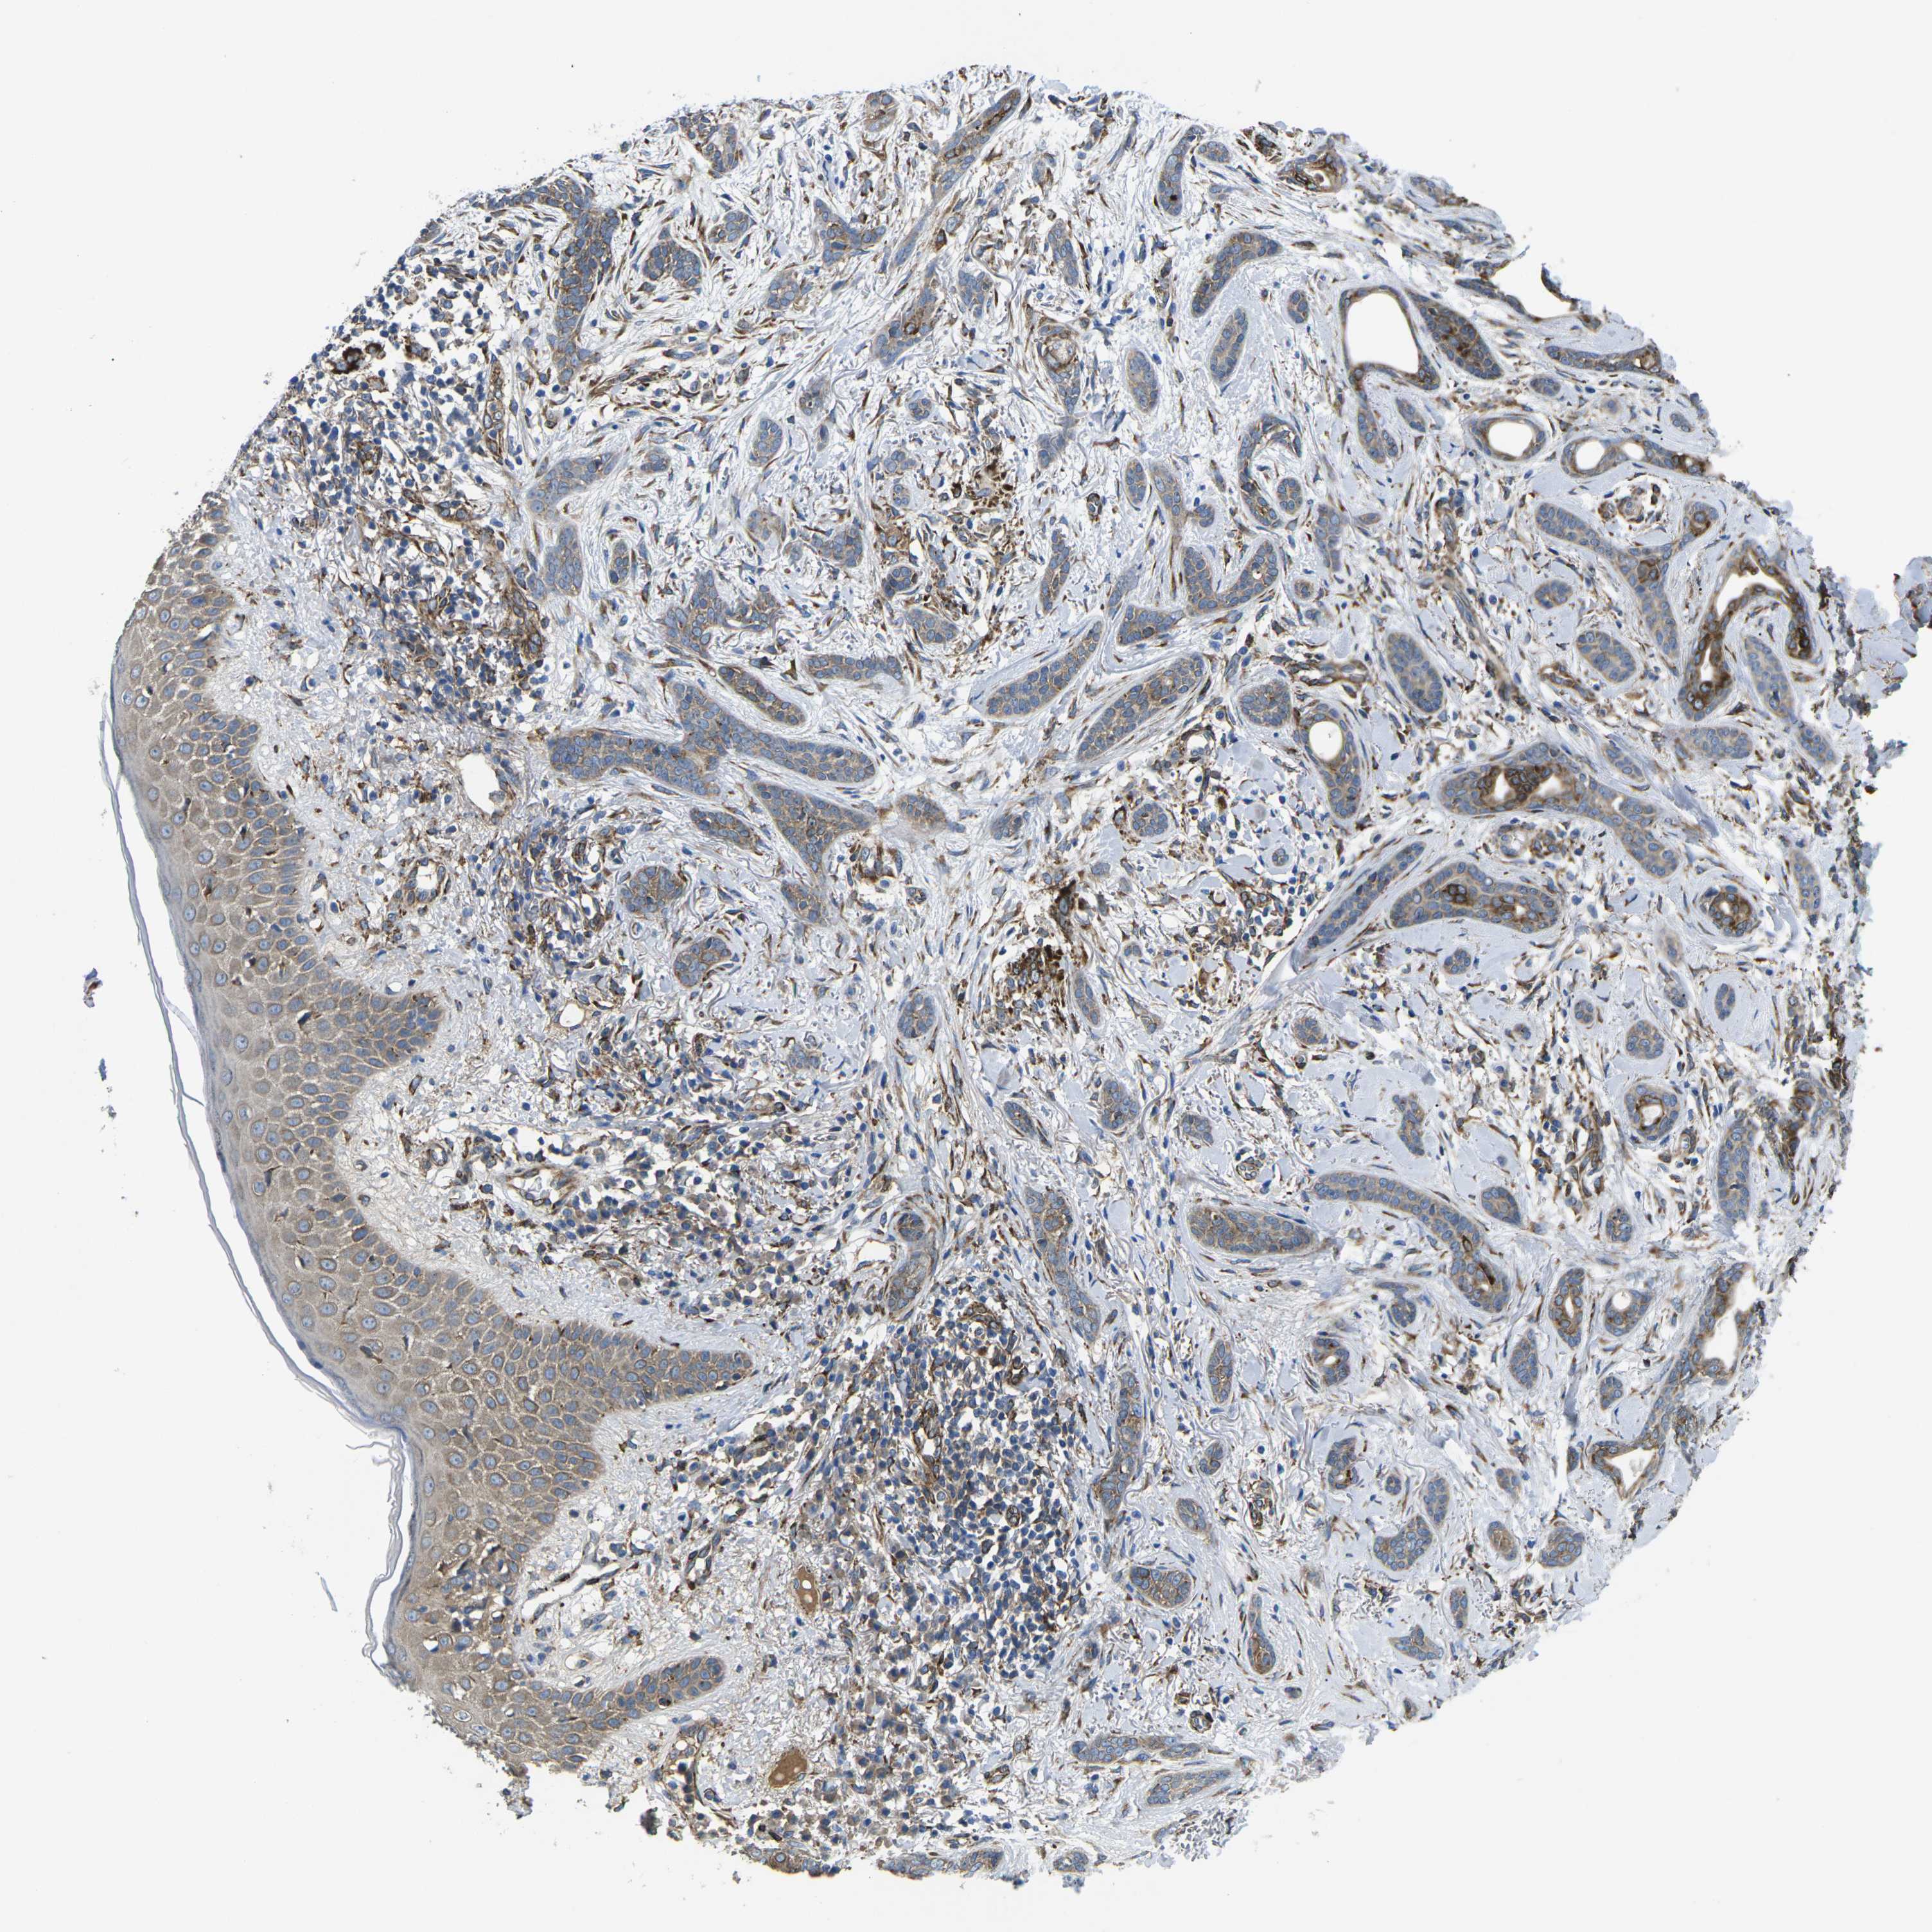

SKIN CANCER - Protein expressioni

A mouse-over function shows sample information and annotation data. Click on an image to view it in a full screen mode. Samples can be filtered based on level of antibody staining by selecting one or several of the following categories: high, medium, low and not detected. The assay and annotation is described here.

Note that samples used for immunohistochemistry by the Human Protein Atlas do not correspond to samples in the TCGA dataset.

Antibody stainingi

Antibody staining in the annotated cell types in the current human tissue is reported as not detected, low, medium, or high, based on conventional immunohistochemistry profiling in selected tissues. This score is based on the combination of the staining intensity and fraction of stained cells.

Each image is clickable and will lead to virtual microscopy that enables deeper exploration of all samples and also displays staining intensity scores, fraction scores and subcellular localization as well as patient and tissue information for each sample.

Antibody HPA015716

Staining

High

Medium

Low

Not detected

Intensity

Strong

Moderate

Weak

Negative

Quantity

>75%

75%-25%

<25%

None

Location

Nuclear

Cytoplasmic/membranous

Cytoplasmic/membranous,nuclear

Squamous cell carcinoma, NOS